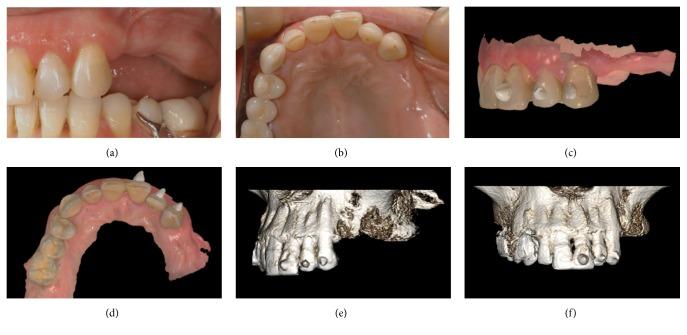

Scope. To demonstrate guided implant placement and the application of fixed, implant-supported prosthetic restorations with a fully digital workflow. Methods. Over a 2-year period, all patients with partial edentulism of the posterior maxilla, in need of fixed implant-supported prostheses, were considered for inclusion in this study. The protocol required intraoral scanning and cone beam computed tomography (CBCT), the superimposition of dental-gingival information on bone anatomy, surgical planning, 3D-printed teeth-supported surgical templates, and modelling and milling of polymethylmethacrylate (PMMA) temporaries for immediate loading. After 3 months, final optical impression was taken and milled zirconia frameworks and 3D-printed models were fabricated. The frameworks were veneered with ceramic and delivered to the patients. Results. Fifteen patients were selected for this study. The surgical templates were stable. Thirty implants were placed (BTK Safe®, BTK, Vicenza, Italy) and immediately loaded with PMMA temporaries. After 3 months, the temporaries were replaced by the final restorations in zirconia-ceramic, fabricated with a fully digital process. At 6 months, none of the patients reported any biological or functional problems with the implant-supported prostheses. Conclusions. The present procedure for fully digital planning of implants and short-span fixed implant-supported restorations has been shown to be reliable. Further studies are needed to validate these results.

范围。展示使用全数字工作流程进行引导式种植体植入以及固定的、种植体支持的修复体的应用。方法。在两年时间里,所有上颌后牙部分牙列缺失且需要固定种植体支持修复体的患者均被纳入本研究。该方案要求进行口内扫描和锥形束计算机断层扫描(CBCT),将牙齿 - 牙龈信息叠加在骨解剖结构上,进行手术规划,制作3D打印的牙齿支持的手术模板,以及为即刻负重制作和铣削聚甲基丙烯酸甲酯(PMMA)临时修复体。3个月后,获取最终光学印模并制作铣削氧化锆框架和3D打印模型。框架用陶瓷贴面并交付给患者。结果。15名患者被选入本研究。手术模板稳定。植入了30颗种植体(BTK Safe®,BTK,意大利维琴察)并即刻用PMMA临时修复体负重。3个月后,临时修复体被全数字制作的氧化锆 - 陶瓷最终修复体取代。6个月时,没有患者报告种植体支持修复体存在任何生物学或功能问题。结论。目前用于种植体全数字规划和短跨度固定种植体支持修复体的程序已被证明是可靠的。需要进一步研究来验证这些结果。